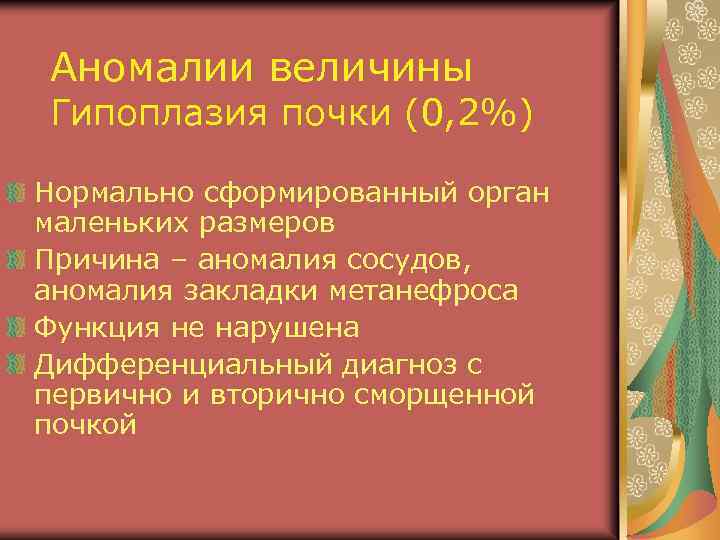

Аномалии величины Гипоплазия почки (0, 2%) Нормально сформированный орган маленьких размеров Причина – аномалия сосудов, аномалия закладки метанефроса Функция не нарушена Дифференциальный диагноз с первично и вторично сморщенной почкой